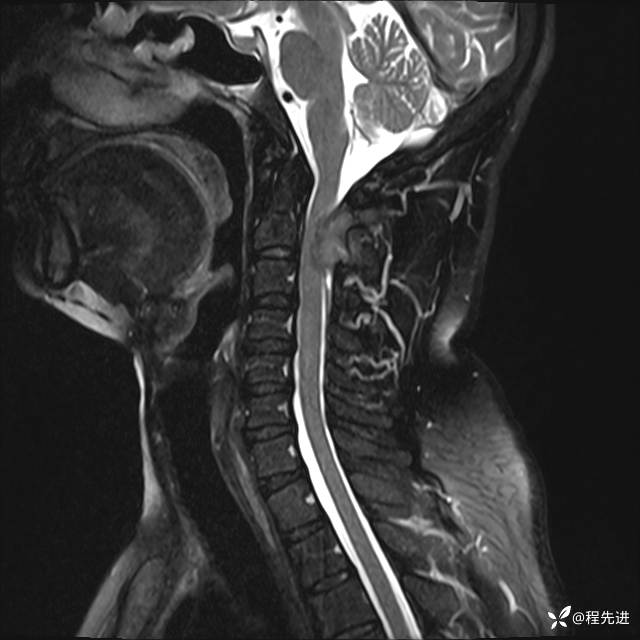

MRI平扫+增强:

T1增强: